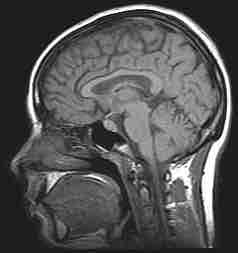

MRI of the human brain

Magnetic resonance imaging (MRI) scans of the head are often used to help psychologists understand the links between brain and behavior.